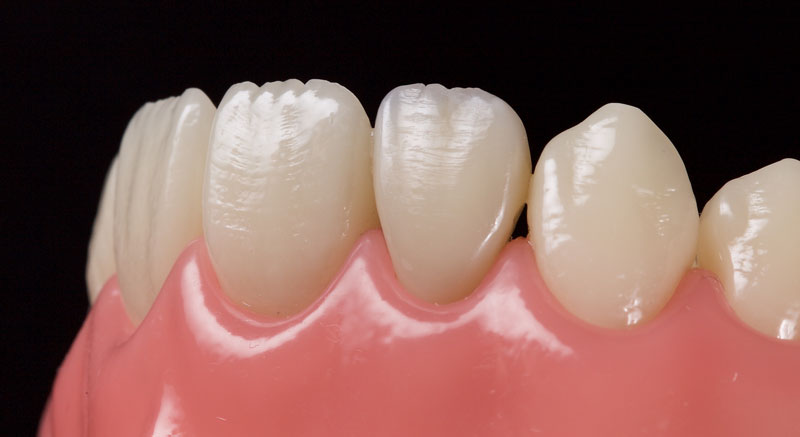

- Single Tooth: This is a microdontia localized to one tooth. Most peg laterals seen in a general dental practice setting will be of this type. See Fig. 3 (pre-op) and Fig. 4 (immediate post-op treated with direct resin).

After a final polish with a felt wheel and aluminum oxide polish (Flexibuff and Enamelise, Cosmedent) at decreasing pressure and increasing speed, the restoration is complete (Figs. 18 and 19.)